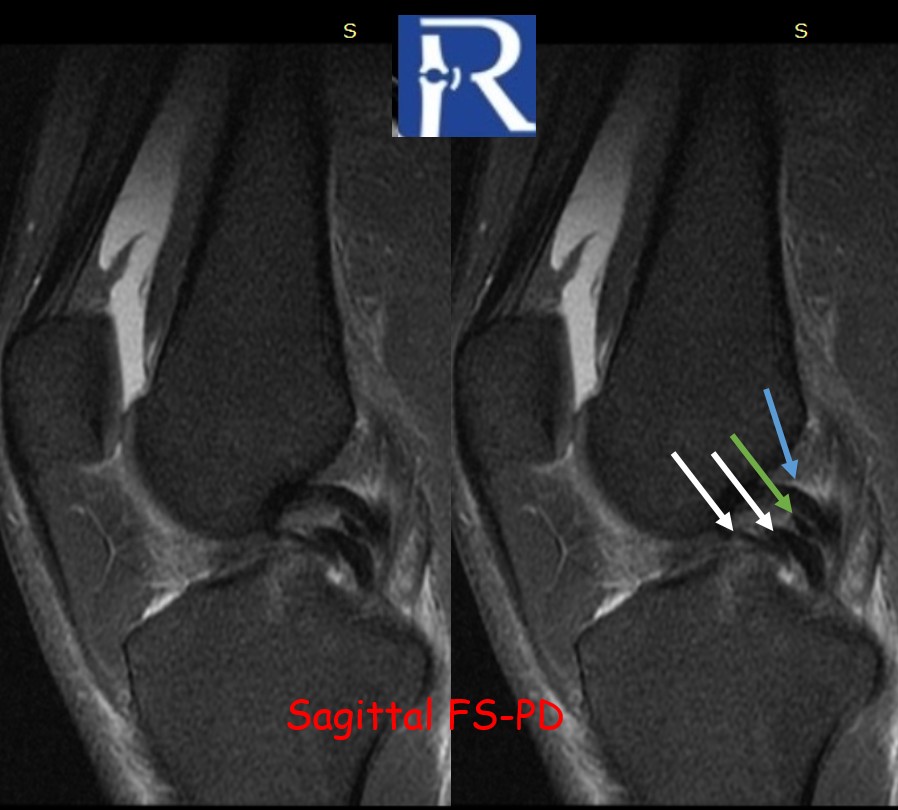

The Forgotten ACL Finding: Stump Entrapment Beyond the Tear in Pivot-Shift Injuries Clinical Context A 46-year-old male presented with acute ...

The arcuate sign is a fibular head avulsion fracture indicating posterolateral corner injury, commonly associated with ACL and PCL tears. Early recogn ...